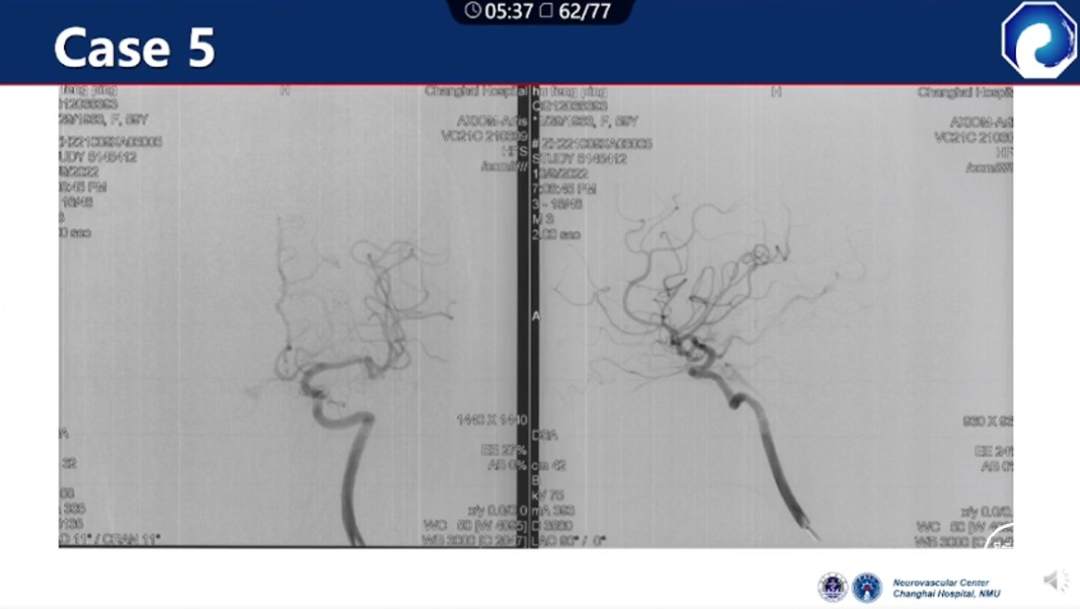

痿口静脉端的识别至关重要。

痿口静脉端精准完全闭塞是DAVF治愈的关键。